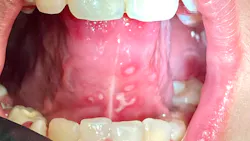

Note: The pictures are not of the highest quality as the patient was in extreme discomfort when I took them.

Differential considerations include:

Definitive diagnosis is likely one of two: Herpangina or acute primary herpetic gingivostomatitis

The saying “nothing is for certain unless it’s in a petri dish” stands true in all pathology cases, including this one. However, based on the symptoms and clinical presentation, I was able to surmise that it was more than likely either herpangina or APHG, although I’m leaning toward APHG.